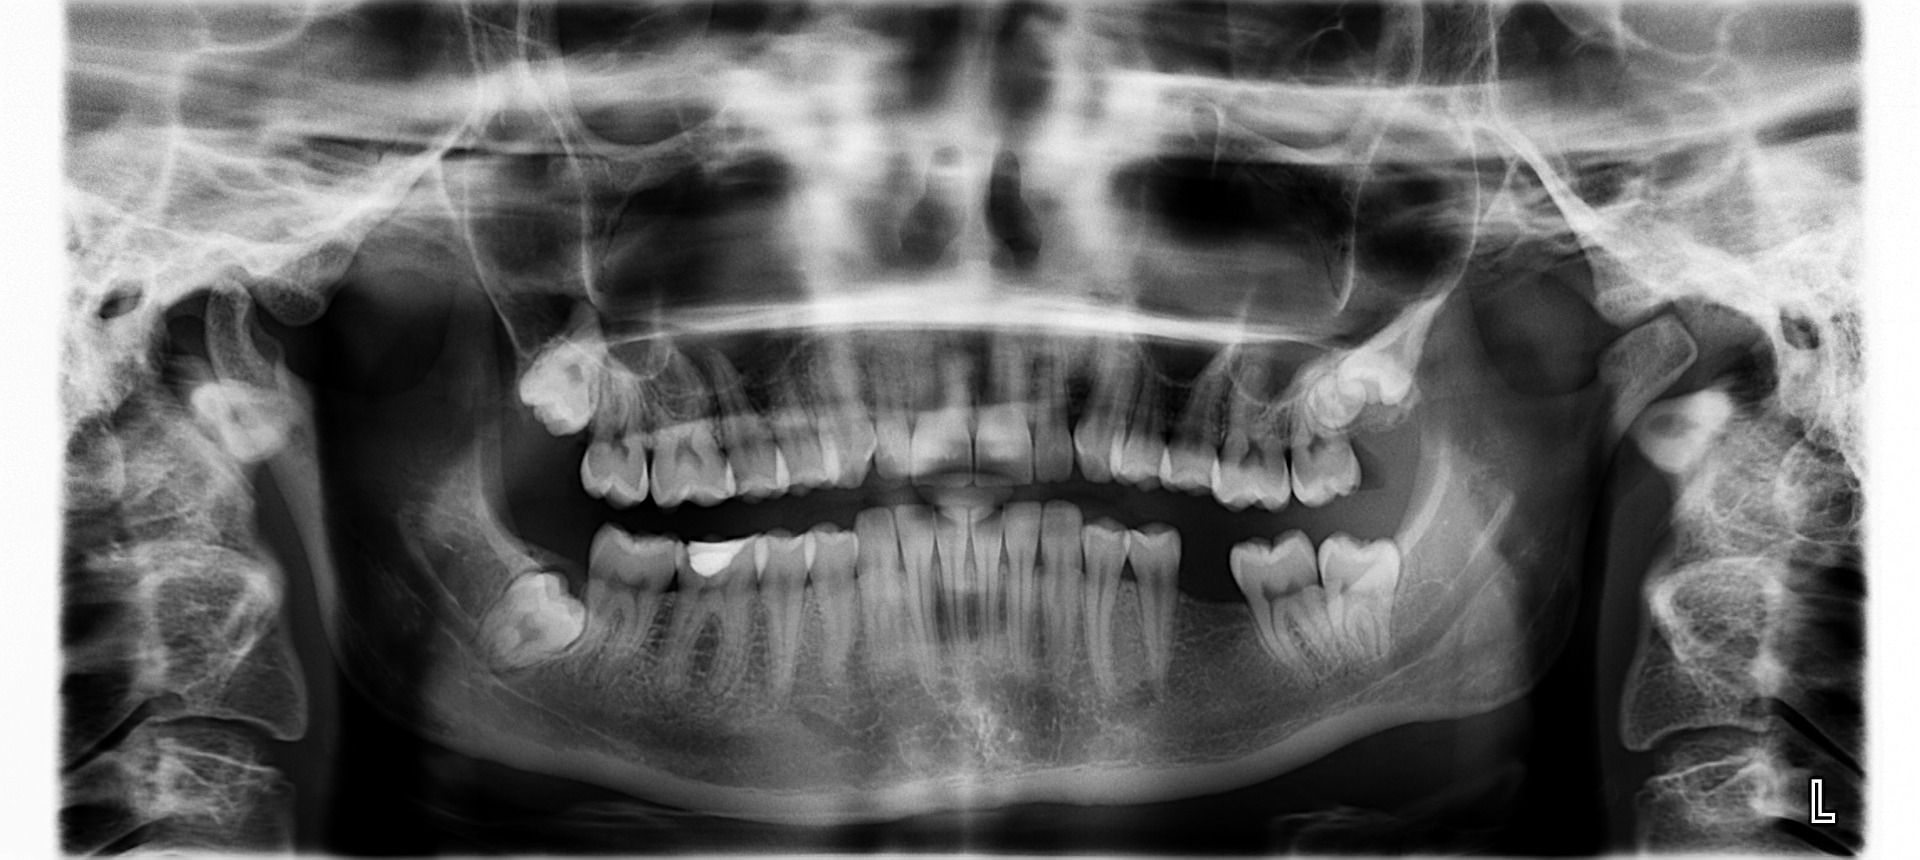

치아가 빠지고 피가 자주 나는 증상이 있습니다. 골다공증 초기에는 턱뼈가 약해져서 잇몸이 상하고 치아건강이 악화되는 현상이 나타납니다.